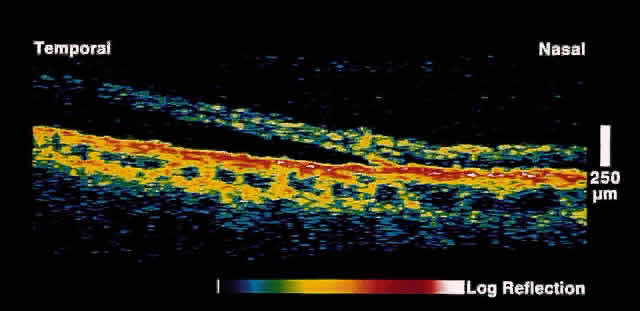

Serous Macular Detachment Secondary to Optic Nerve Pit Optical coherence tomography images of this clinical entity clearly demonstrate

the relation between the optic nerve pit and serous macular detachment (Fig. 4). These images support the concept that fluid from the optic pit directly

enters the neurosensory retina and not the subretinal space.13  Fig. 4. OCT image through macula and optic disc in a patient with an optic nerve

head pit. The optic pit is contiguous with a schisis-like cavity in

the inner retina and not with the subretinal space. Fig. 4. OCT image through macula and optic disc in a patient with an optic nerve

head pit. The optic pit is contiguous with a schisis-like cavity in

the inner retina and not with the subretinal space.